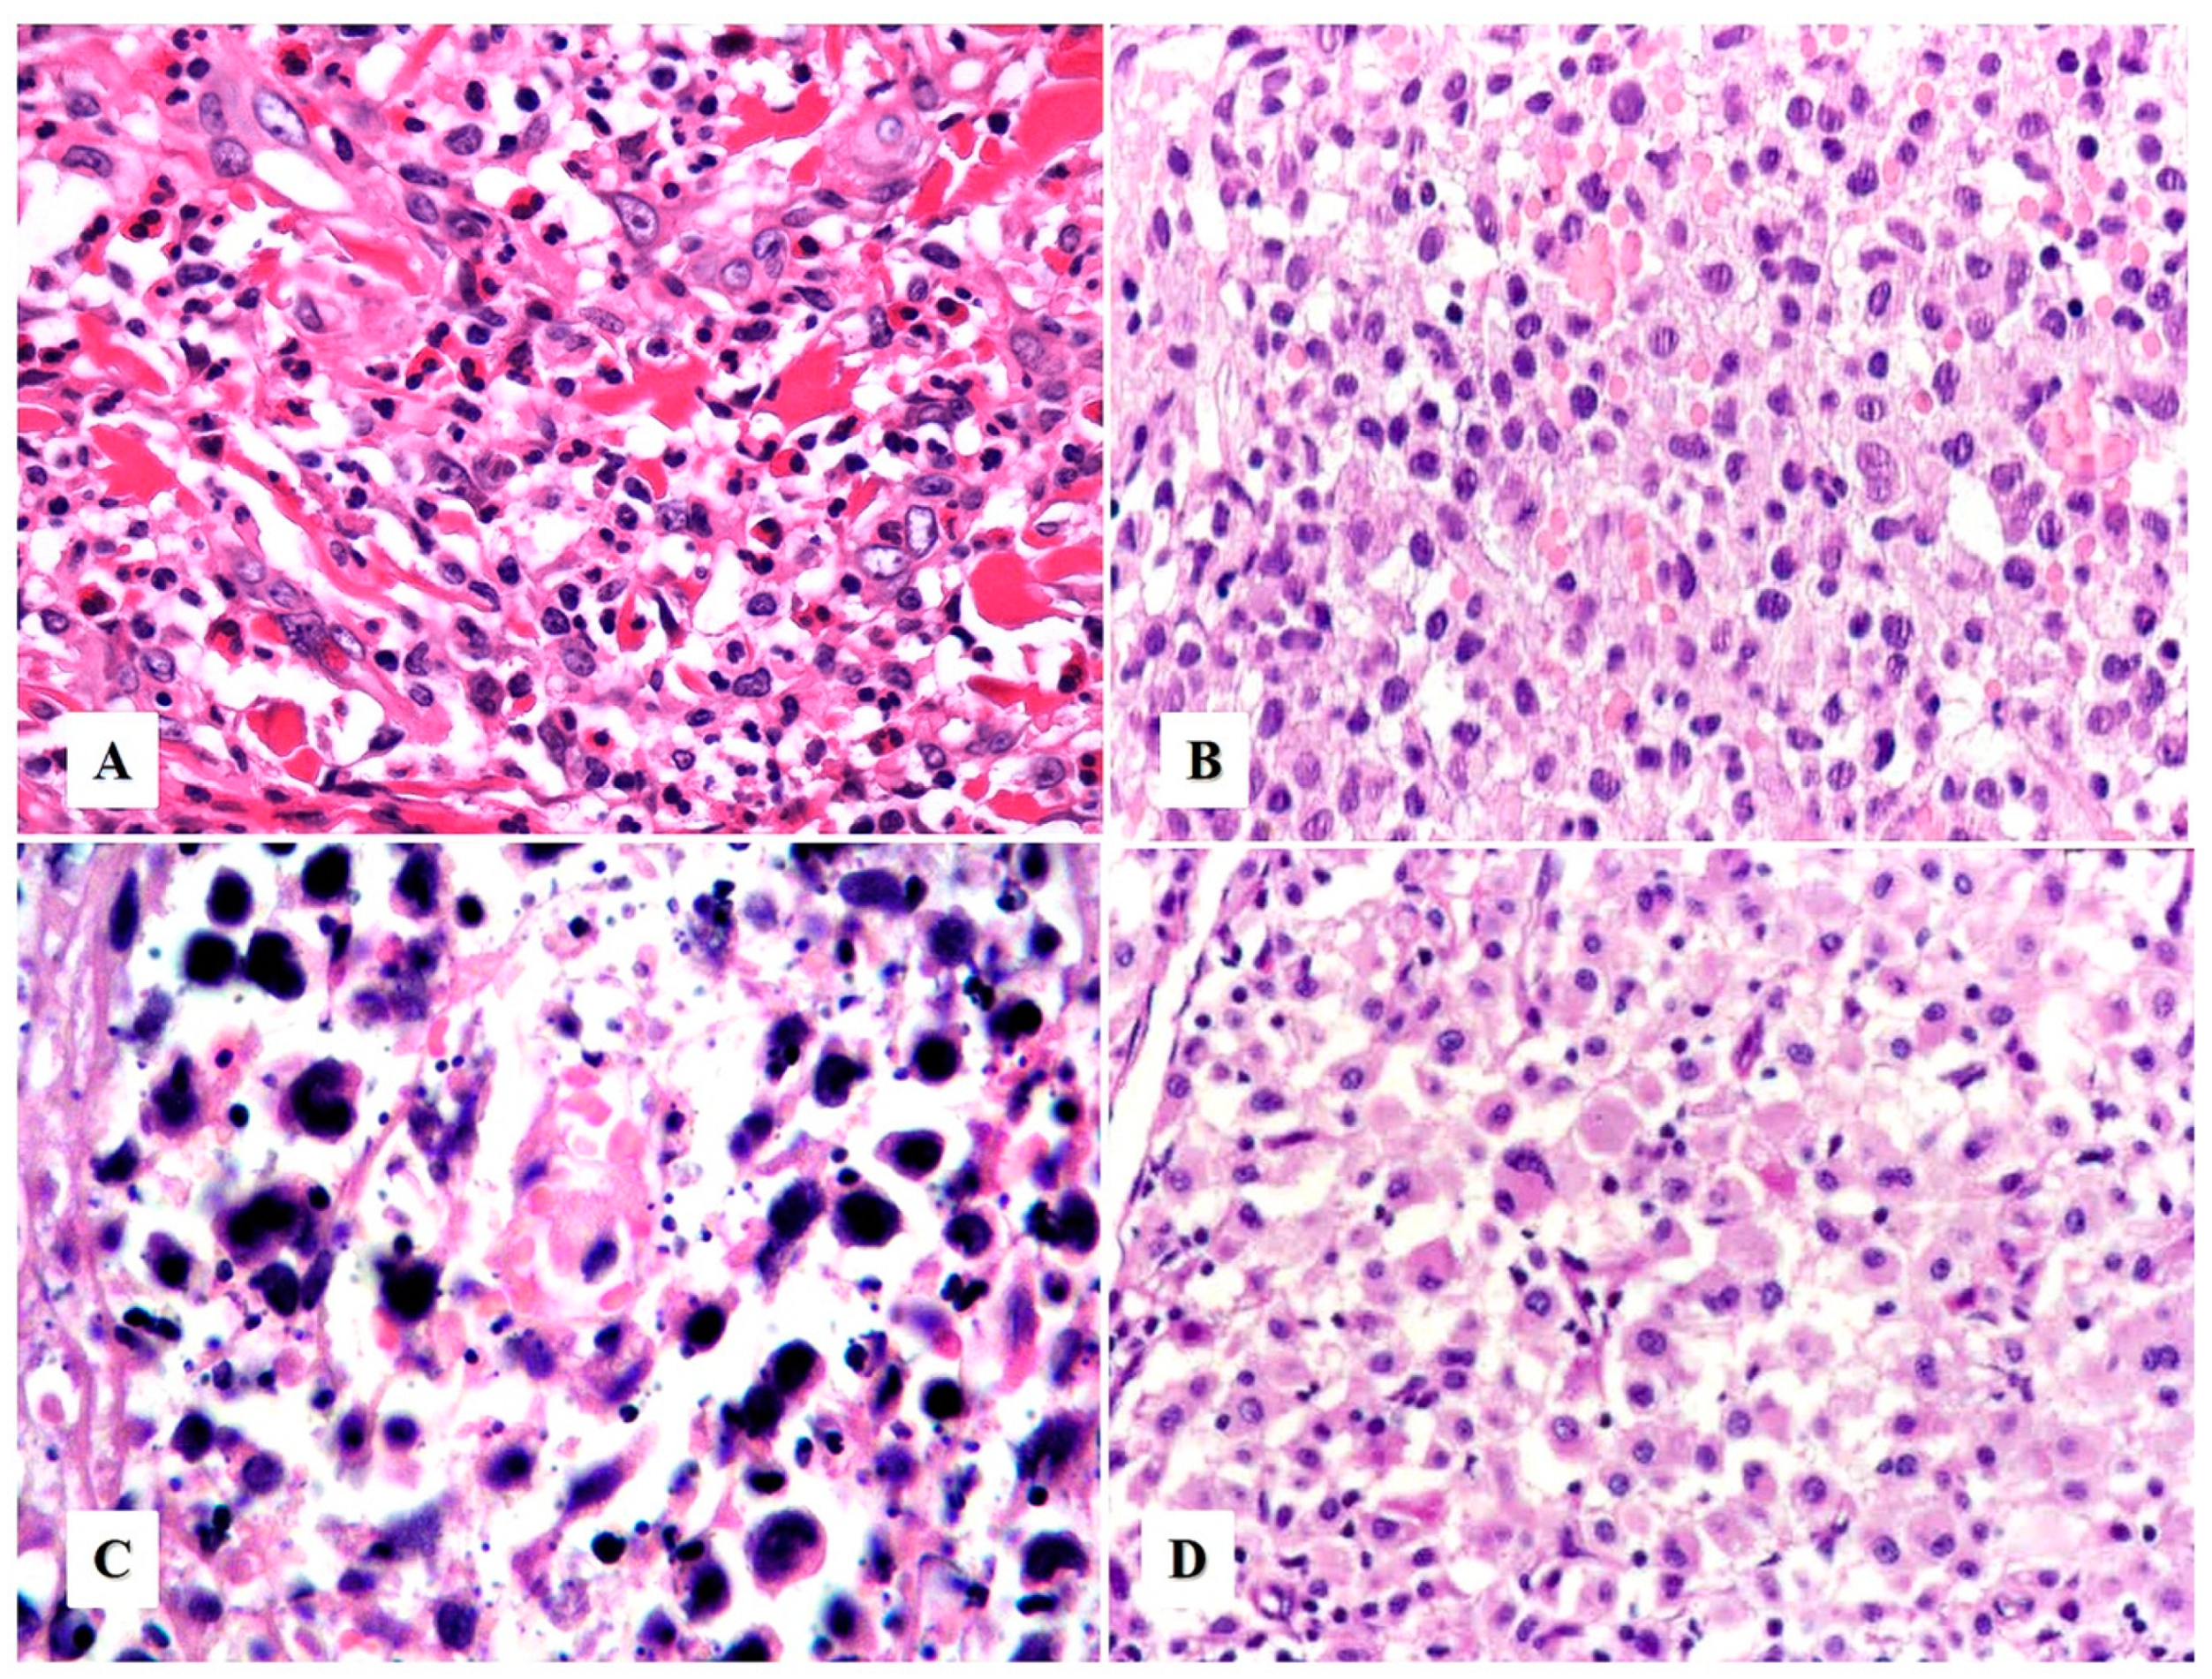

Morphologic Variants of Primary Cutaneous ALCL